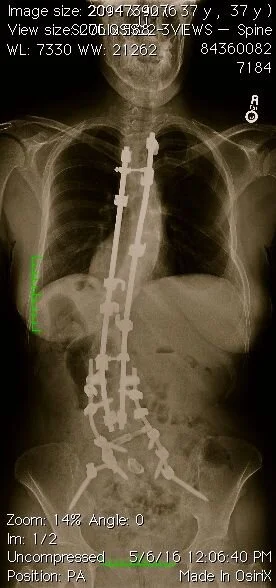

Did you know yoga can be practiced by a person with steel and titanium rods from their neck to their hips? Well, it can and one of those persons is me, Star Kolb. I have scoliosis, an extreme curvature and rotation of the spine and I practice yoga.

In my yogic education from the Rocky Mountains to the Himalayas, I practiced and taught the ancient and modern approaches of yoga. In Moab, I learned to meditate daily with mantra. In my Thai jungle hut, I learned self discipline by practicing from dawn to dusk. In my fly infested yoga ashram in Rishikesh, India I learned complete stillness in final relaxation. There have been times when I’ve practiced yoga on my head, and at other times I was only able to practice from my bed, always watching and disciplining my breath, my thoughts. Today, four spinal fusions later and grateful for every step. I feel this is possible because I continue to practice yoga.